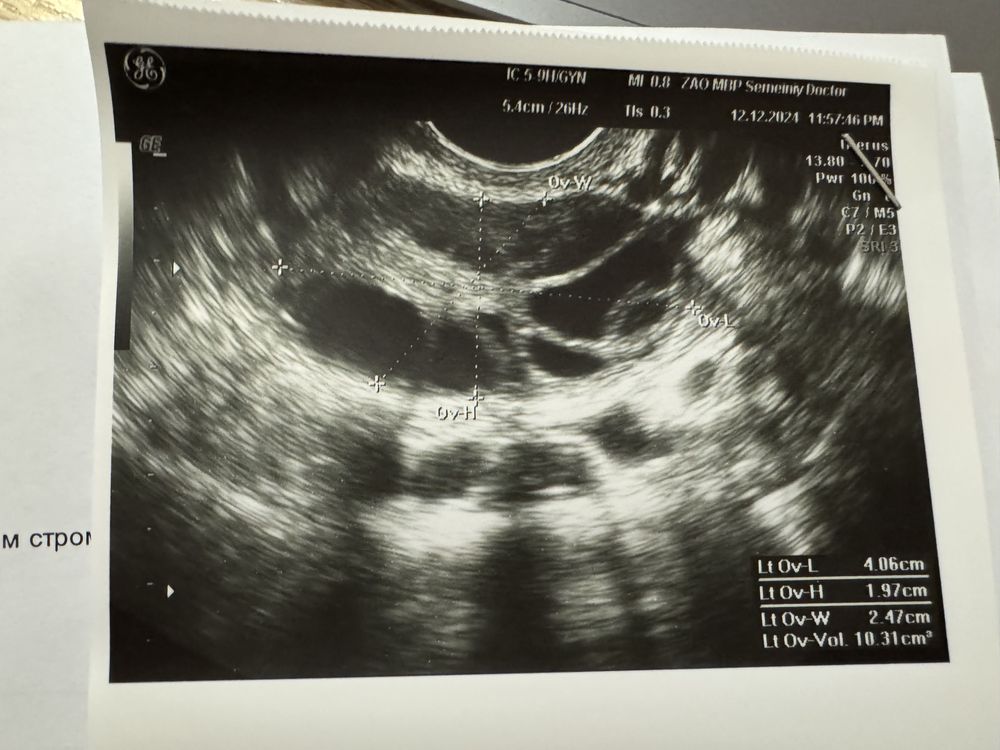

Изображение Изображение